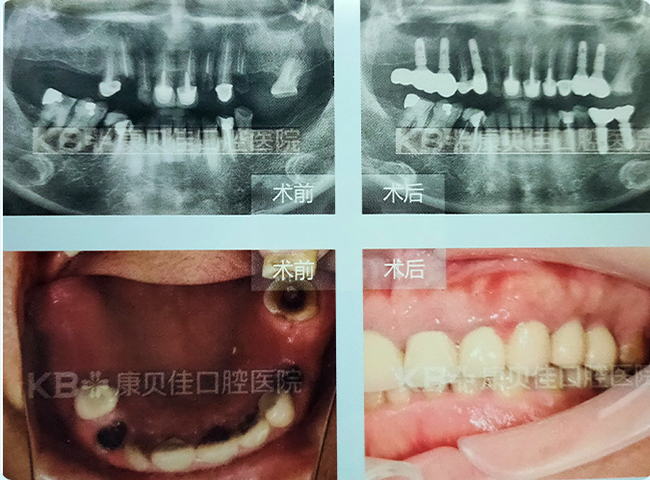

肖女士 70岁

因为牙周病导致全口牙齿逐渐松动、脱落,以前喜欢吃的排骨、酱鸭、猪蹄等美食已经很多年没有吃过了。由于营养跟不上,体质也不是很好。到院后检查发现其牙槽骨条件非常差,种植难度大。经过会诊,医生为她定制了即刻恢复方案,当天就帮她恢复了一口好牙,现在什么都能吃,身体也越来越好了!

治疗方案:

上颌种植6颗恢复半口 下颌种植4颗恢复半口